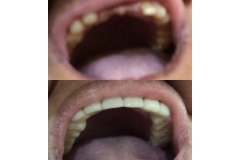

Tooth restorations are the various ways your dentist can replace missing teeth or repair missing parts of the tooth structure. Tooth structure can be missing due to decay, deterioration of a previously placed restoration, or fracture of a tooth.

Both crowns and most bridges are fixed prosthetic devices. Unlike removable devices such as dentures, which you can take out and clean daily, crowns and bridges are cemented onto existing teeth or implants, and can only be removed by a dentist.